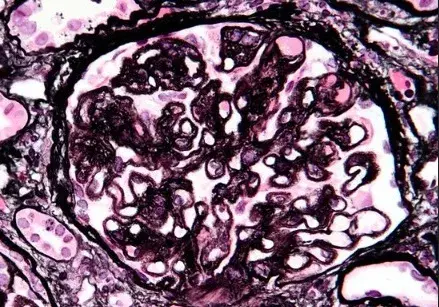

A imunofluorescência mostra marcação linear de IgG na MBG (anticorpo anti-IgG; 400×).

A imunofluorescência demonstrou padrão de deposição linear de IgG (policlonal), deposição na membrana basal glomerular (MBG), sem depósitos na microscopia eletrônica.